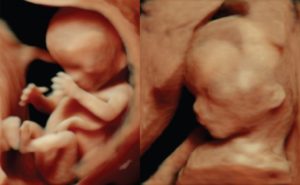

• Размер плода к 12 неделе достигает 6 см, а весит малыш не более 13 гр. Несмотря на такие крошеные размеры, на фото эмбриона (плода) во время УЗИ уже четко видно, что внутри нас – настоящий человек: с головой, туловищем, тоненькими ножками и ручками.

Беременность в 12 недель означает, что развитие внутренних органов плода произошло и они продолжают расти дальше. К началу 12 недели размер плода составляет примерно 6 см. За эти 7 дней он подрастет еще на 1-2 см. Все основные ткани и органы малыша развиты, теперь он активно питается через плаценту. Это значит, что самый опасный период его эмбриональной жизни прошел.

На 11 неделе беременности кости малыша представляли собой мягкие хрящики. В 12 недель беременности развитие плода и его костной структуры продолжается, кости становятся все более твердыми. Это сопровождается увеличением веса плода, всего за неделю он подрастет от 15 до 20 г.

До сих пор голова плода непропорциональна телу, но с каждой неделей малыш становится все больше похож на младенца. Меняется и лицо ребенка, глазки, которые сначала были расположены ближе к бокам, начинают сближаться. Развиваются ушные раковины.

Плод на 12 неделе беременности имеет массу приблизительно девять-тринадцать грамм. Хотя он и активно двигается в околоплодных водах, беременной девушке сложно почувствовать его – плод пока слишком мал.